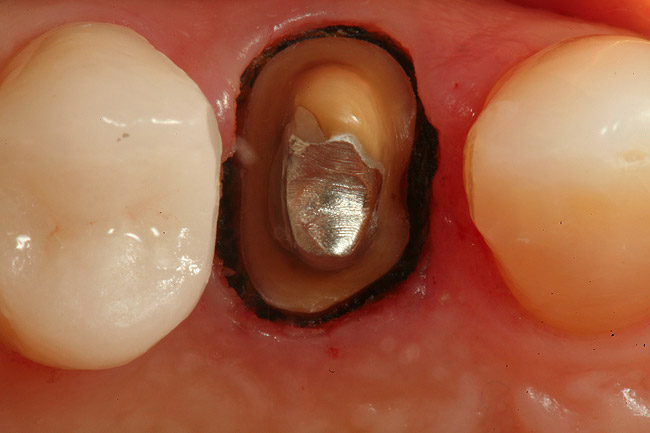

Again, use the needle electrode on the electrosurgery unit to limit the zone of necrosis. It is the author’s opinion that troughing is an excellent adjunct to mechanical retraction and most of the time when troughing, he will “lay” a cord in the sulcus after troughing to help push away any small tissue tags that can remain and further aid in hemostasis. The goal of retraction is to have a “moat around the castle,” or unimpeded access to the sulcular area for the impression material to flow. The maxillary premolar in Figure 11 had a post and core placed and is ready for master impression. Due to the subgingival margin position on the lingual aspect of the preparation and thickness of the interproximal tissue, the proximal and lingual aspects of the preparation were troughed with the electrosurgery needle electrode (Figure 12 and Figure 13). After sounding to the crest of bone to verify that biologic width was not encroached upon (Figure 14), a #1 retraction cord soaked in a hemostatic agent was “laid” into the sulcus (Figure 15). The only “packing” of cord took place on the facial where due to the thinness of the tissue, troughing was not done. Figure 16 shows a totally patent gingival sulcus with no signs of hemorrhage, ready for placement of impression material. Figure 17 shows a master impression taken after a troughing/retraction procedure on tooth No. 5.

Figure 11  An occlusal view of tooth No. 5 after preparation has been made for a full-coverage restoration.

Figure 12  The needle electrosurgery electrode was used to "trough" around the lingual of the preparation to expose the preparation margin.

Figure 13  Troughing was completed on the proximal and lingual aspects of the preparation to aid in retraction cord placement prior to making the master impression. The marginal gingiva on the facial aspect was too thin to perform troughing without risking vertical loss of tissue.

Figure 14  The restorative margin on the lingual aspect of the preparation is measured at 3 mm from the bony crest; therefore, no resective bony procedure was required.

Figure 15  First, a #00, then a #1 retraction cord was "laid" into the troughed space between the preparation margin and the circumarginal gingival tissue.

Figure 16  The #1 cord was removed from the sulcus, the #00 remained in place during the making of the master impression. A fully patent sulcus is seen 360° around the preparation.

Figure 17  The master impression is shown. The restorative margin and 0.5 mm of tooth or root surface (emergence profile) is clearly visible in the impression.

Figure 18  Troughing was performed on the distal of tooth No. 31 so that the margin and tooth surface apical to the preparation will be accessible to the light-bodied impression material.

Figure 19  The master impression for tooth Nos. 30 and 31 are shown.

Figure 20  Electrosurgery was performed on the distal of this onlay preparation to gain unimpeded access for the impression material. Note that it is imperative that the biologic width (epithelial and connective tissue attachments) not be disturbed.

Figure 21  The retraction cord was placed around the preparation after the troughing procedure was completed.

Figure 22  The master impression for the onlay preparation is shown.